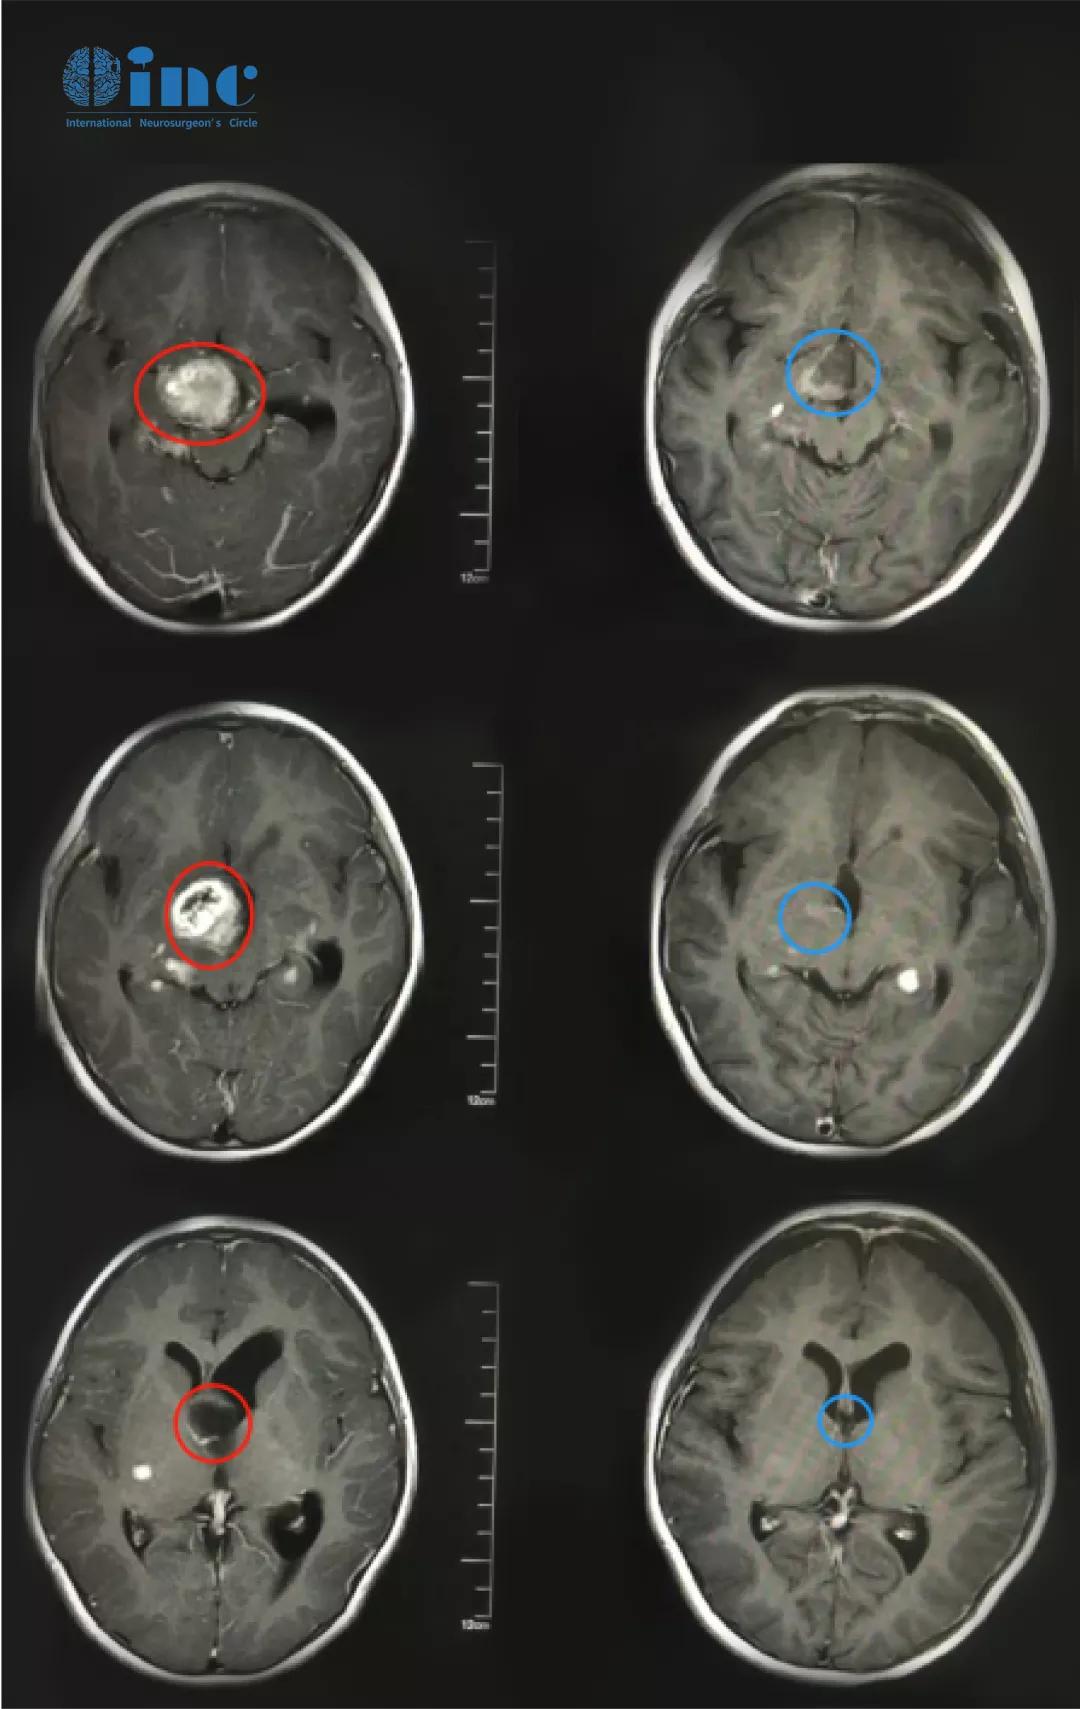

康康的术前术后MR影像对比

术后情况:康康在ICU观察了一夜第二天就转到普通病房,术后第二天就能顺利转出普通病房揭示了手术的巨大成功,因为这样的手术是非常疑难的,靠近下丘脑、脑干,这样大的肿瘤切除引起术后脑水肿、脑出血、呼吸障碍及内分泌功能紊乱的几率是极大的,但是巴教授的高超技术就是可以如此好的保护好这些“宝贝”, 最大程度切除肿瘤而不损伤神经。术后复查MR显示肿瘤得到次全切除,孩子的原有视力得到保留。目前术后恢复良好,无新发神经功能损伤。术后病理结果为毛细胞粘液样型星形细胞瘤,这属于WHO二级胶质瘤,也意味着康康配合术后化疗以及后期的新型放疗可以得到比预期更好的预后。目前,康康正在接受进一步的化疗,日常的生活起居基本恢复。

术中情况:由巴特朗菲教授主刀携国内专业手术团队成功为康康次全切巨大视路胶质瘤,双侧视神经、下丘脑、脑干区域内肿瘤次全切除,仅神经表面参与小部分肿瘤,术中行神经电生理监测、术中神经导航技术。

当胶质瘤累及视神经-下丘脑,到底是选择手术还是放化疗?康康的视力已经岌岌可危,还有手术全切肿瘤并保住视神经的可能吗?还有办法保住视力吗?幸运的是,为追求最后的生存希望,也为尽可能地保住现有视力,一家人找到INC德国巴特朗菲教授治疗。作为2021年巴特朗菲教授来华疑难手术示范的第一个病人,康康的肿瘤得到了次全切,术后逐渐恢复,最让所有人吃惊的是,他的原有视力得到了保留。